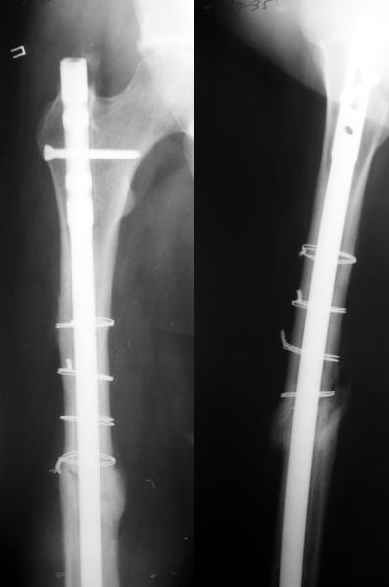

1) Мы бы не убирали проволоку, и вообще не вмешивались открыто на очаге - это ничего не даст, кроме ухудшения кровоснабжения концов отломков. Если просто закрыто перештифтовать при подобной картине, лучше с рассврливанием - это по нашему опыту дает сращение в 100%. В приложении пример - болезненное несращение более года, результат через полгода.

1

2